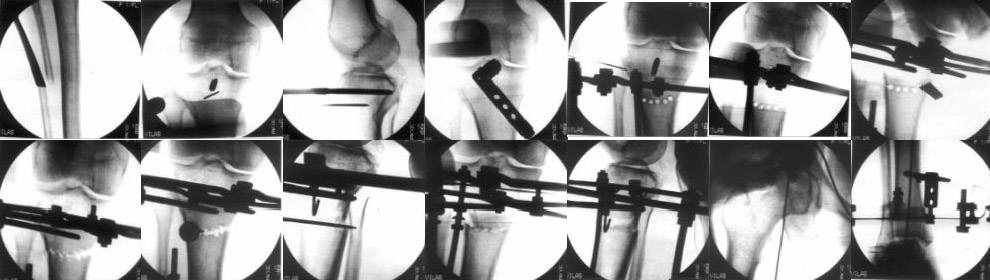

The frame I use is pretty simple, with one wire each in the proximal and distal ring, two schanz pins in the proximal ring, and one each in the middle and distal ring.

I preconstruct a frame with the proximal ring in varus by the use of coupled washers in the threaded rods in the front and back. These are used as hinges, and after the correction, a medial and lateral threaded rod is also added.

Since the center of rotation of these deformities is usually near the knee joint line, lateral translation of the distal fragment is necessary to normalise all the axes.